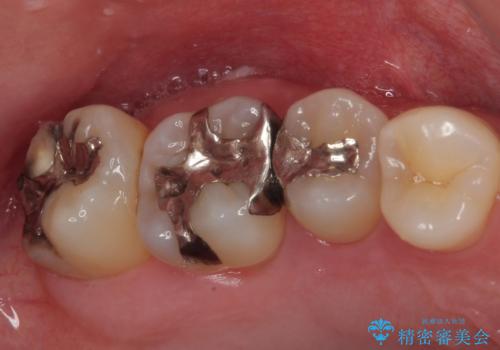

- 奥歯が食事中に歯が欠けて、しみて痛いとのことで来院された患者様です。

レントゲン写真からも、舌側に大きな虫歯があることが分かりました。

症状から神経を取り除く可能性も考慮し、オールセラミッククラウンにて補綴治療することとしました。